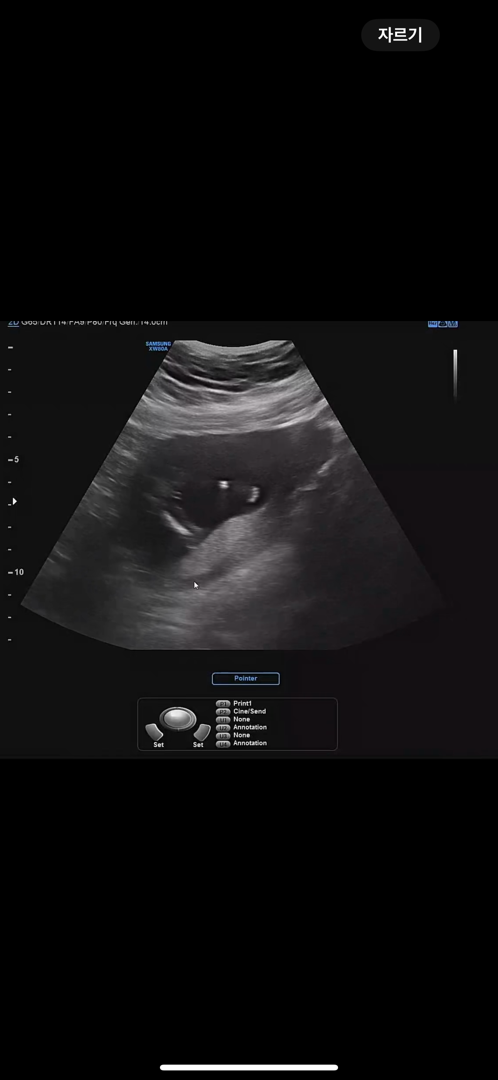

15주 초음파

딸일까요? 안들일까요?! 친구는 고추가보인다고 하는데 너무작아보여서ㅎㅎ 딸둘맘이라 아들이였으면 하는데...ㅎㅎ

딸인것같아요! 점두개는 딸이고 점세개가 아들이래요